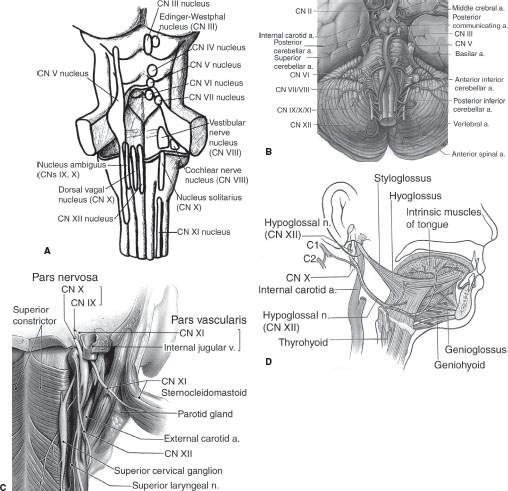

Motor Cranial Nerves – Anatomy, Functions & Components | Kenhub

Hypoglossal nerve-Functional component-Nucleus-Course-Distribution …

Hypoglossal Nerve – Location, Function, Origin and FAQs

Motor cranial nerves: Anatomy, functions and components | Kenhub

Hypoglossal Nerve – AnatomyZone

The Hypoglossal Nerve (CN XII) – Course – Motor – TeachMeAnatomy

Hypoglossal Nerve (CN-XII)

Neuroanatomy, Cranial Nerve 12 (Hypoglossal) – StatPearls – NCBI Bookshelf

Hypoglossal Nerve

Hypoglossal Nerve Intermedullary Course

Hypoglossal Nerve Intermedullary Course

Hypoglossal Nerve (CN-XII)

Hypoglossal Nerve (XII) and Canal

Hypoglossal Nerve (CN-XII)

Hypoglossal Nerve (XII)

Hypoglossal Nerve (CN-XII)